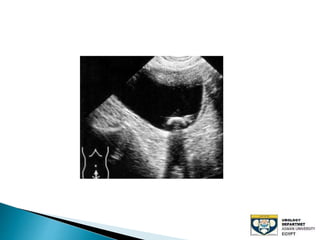

The document discusses urinary tract stones, detailing their types, causes, symptoms, and diagnostic methods. It highlights the risk factors such as infections and obstructions, with men being more commonly affected. Treatment options include various surgical methods, particularly for managing bladder outflow obstruction and lithiasis.